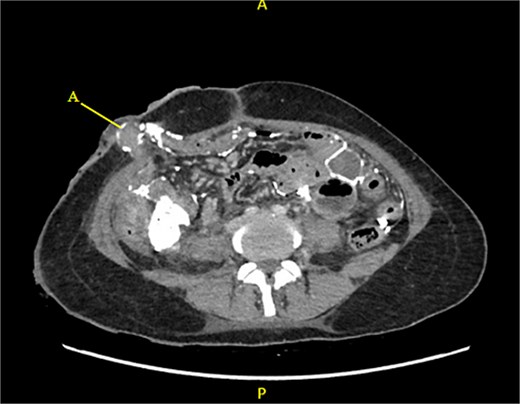

Contrast-enhanced CT of the abdomen and pelvis revealed extensive barium extravasation outlining the peritoneal cavity, accompanied by pneumoperitoneum (Fig. 3). Two barium-outlined, walled-off intra-abdominal collections were identified: one located anterior to the lower pole of the left kidney and the other in the pelvis, anterior to the rectum (Figs 4 and 5). Due to significant barium-related imaging artifacts, the precise site of bowel perforation was not identified. A diagnosis of peritonitis secondary to barium spillage was established, with associated intra-abdominal collections.

CT contrast abdomen and pelvis showing spill of barium outlining the peritoneal cavity. Stoma at the right side of the abdomen (A).

CT-guided percutaneous drainage was performed for the intra-abdominal collections (Fig. 6), and cultures of the drained fluid revealed heavy growth of Escherichia coli and Enterococcus species. Her medical history also revealed incomplete antibiotic treatment for the preceding typhoid infection, prompting the initiation of empiric meropenem. Following consultation with the infectious diseases team, her antibiotic regimen was tailored to include tigecycline based on culture sensitivities and her typhoid history.